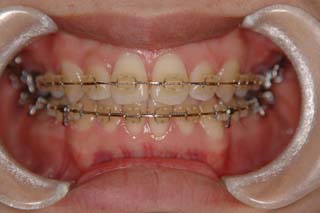

診断名:叢生を伴う上下顎前突

上顎前歯、下顎前歯の前突が見られます。大きな叢生は見られませんが、上下の口唇前突感も伴います。このような不正咬合を上下顎前突と言います。審美的な事もさることながら、歯軸の傾斜の問題から歯にかかるベクトルが良くない事、口唇の筋肉の緊張を強いるような不調和を示す事などから、不正咬合の一つとして考えられています。上顎前突傾向も伴っていますので、積極的に上顎前歯の後退を行う目的で、上顎に固定源となる 目的外使用の オーソアンカー SMAPシステム を装着しました。現在では、歯科矯正用アンカースクリュー(デュアルトップオートスクリュー、ISAアドバンスなど)といった、医療機器認証番号がある製品を用いることが多くなりました。

一般的なマルチブラケット装置を用いた治療では、先ずは形状記憶合金のワイヤーで大まかに配列を行い、バネをきかせたワイヤー、堅いワイヤーを使って仕上げていく方法です。